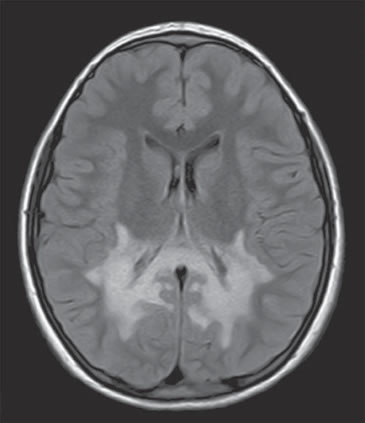

Debido a la rápida progresión de su estrabismo, se solicita RN cerebral, que muestra leucoencefalopatía con marcada alteración de la sustancia blanca periventricular a nivel atrial, que se extiende a los cuerpos geniculados laterales, a las radiaciones ópticas, alrededor de los cuernos occipitales y al esplenio del cuerpo calloso con compromiso de los tractos córtico espinales desde el mesencéfalo hasta la protuberancia (Figura 1).

Figura 1. Resonancia Nuclear cerebral. Se observa una leucoencefalopatía con marcada alteración de la sustancia blanca periventricular, que se extiende a los cuerpos geniculados laterales y radiaciones ópticas alrededor de los cuernos occipitales.